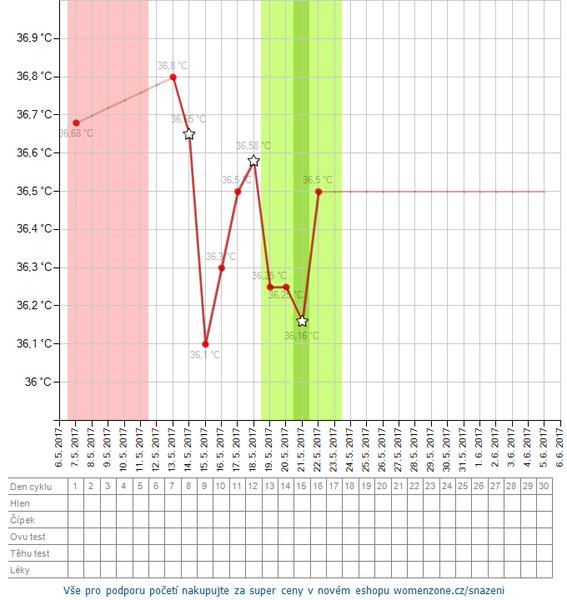

Inofolic, inositol tablety, Nosifol (kyselina listová), Gynex, Femibion, Femibion1, pupalka dvojročná, vitamin E so selenom, „vitez jahnaci“, maca, rakytníkový olej, rebríčkový čaj, alchemilkový čaj, ovulačné testy (Pepino, Rapiclear, Women secrest), tehotenské testy (spomenuté: Clearblun), Urinal Akut Forte, Paralen, norethisteron, clostylbegit, folikulometria, ultrazvuk/sono, krvné testy (vrátane hCG), močová kultivácia, laparoskopie, IUI, IVF, BT (meranie bazálnej teploty), biochemické tehotenstvo, kyretáž, infúzia

Ovulku mavam 16dc a cyklus doposial bol pravidelny 28dnovy ale posledne dva mesiace na 32dc dosla mrcha. Odkedy berem closttil.